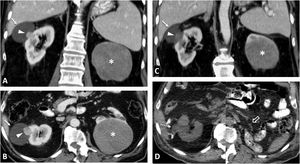

Birt-Hogg-Dubé syndrome. A 68-year-old male. Incidental finding in an ultrasound examination. (A) Ultrasound centred on a lesion. In B-mode (arrow) it is discreetly hypoechogenic, with contrast enhancement (red ROI), purely intravascular, almost as intense as that of the renal parenchyma (yellow ROI), both in the static image and in the time-intensity curve (not shown). Core needle biopsy was performed on this lesion and on another lesion (not shown), with histological diagnoses of a chromophobe cell renal carcinoma and an oncocytic lesion. (B) CT Multiple focal bilateral renal lesions of various sizes and well demarcated (at least six were identified) with moderate enhancement, somewhat weaker than that of the renal parenchyma and more intense in the corticomedullary phase (arrows). One had some small focal calcification (not shown). Thin-walled cysts are also visible at the lung bases (arrowheads). (C) MRI centred on the larger lesion (arrows). It shows signal intensity in T1 (similar for in-phase and opposed-phase sequences) and T2, as well as moderate water diffusion restriction, with an average ADC value of 0.91 × 10−3 mm2/s and clearly less intense enhancement than that of the renal parenchyma in the time-intensity curve (ROI and red and yellow curves, respectively). The genetic study confirmed a germline mutation of the FLCN gene in heterozygosis.